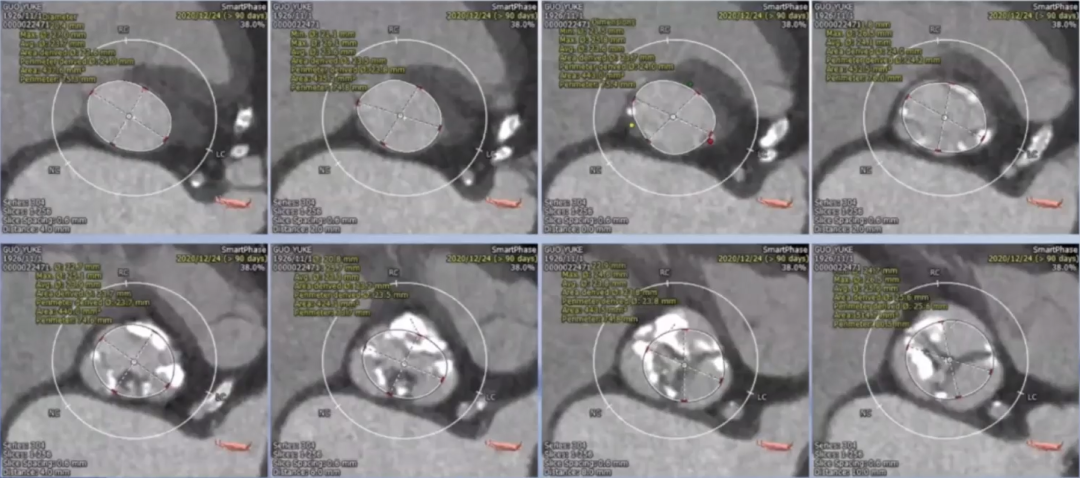

患者为94高龄老年男性患者,5年前出现胸闷憋喘,活动后明显,诊断为主动脉瓣钙化并重度狭窄,1年前症状加重,药物治疗好转后半年前再次加重。术前超声检查结果显示,主动脉瓣平均跨瓣压差63 mmHg;峰值流速5.02 m/s,左室射血分数29%,心功能极差,诊断为主动脉瓣钙化、重度狭窄并轻、中度反流。且患者合并有心力衰竭、冠脉支架病史、高血压三级、右侧髂总动脉闭塞等。术前CT结果显示,瓣环平均直径24 mm,左室流出道直径24 mm,主动脉瓣窦部内径约30 mm左右,STJ为30 mm左右,左、无冠窦存在钙化融合迹象,左冠开口高度14.1 mm,右冠开口高度11.8 mm。

瓣下平均直径约为24 mm,瓣上平均直径也约为24 mm,瓣上6 mm及8 mm处为可能的锚定点。综合患者实际情况及瓣膜特点,计划选择TaurusElite 23 mm可回收瓣膜。

术中采用局麻强化策略,使用右侧股动脉入路,成功穿刺后,首先置入20 F大鞘,并于大鞘中置入一个5 F鞘管和一个10 F鞘馆。使用10 F鞘馆送入导丝,成功完成跨瓣操作,并使用5 F鞘管送入猪尾导管到达主动脉根部。随后沿导丝送入20 mm球囊,180次/min快速起搏下行球囊预扩张,同时进行主动脉根部造影,造影结果显示,预扩球囊腰征明显,无瓣周漏,冠脉亦未受影响,可以选择TaurusElite 23 mm可回收瓣膜。

首次释放瓣膜尝试零位释放,当瓣膜释放到一半时行主动脉根部造影,发现瓣膜释放位置偏低,遂回收瓣膜重新定位后再次释放,当瓣膜释放一半时再行主动脉根部造影,发现瓣膜位置良好,遂完全释放瓣膜。

在瓣膜型号的选择方面,根据术前CT结果可以发现,患者瓣环直径与左室流出道直径均在24 mm左右,但瓣环平面上方4 mm处就开始出现瓣叶融合的情况,左无之间、左右之间都存在未能完全打开的瓣叶,这些瓣叶是否能打开,影响了最终瓣膜型号的选择。但从融合处的钙化情况来分析,瓣叶打开的可能性不大,当不能打开瓣叶时,主动脉瓣下方直径24 mm,上方直径约22 mm,因此选择23 mm瓣膜是合理的。同时,考虑到今天使用的瓣膜为TaurusElite可回收瓣膜,其23#瓣膜的底边直径为24.5 mm,完全可以贴合瓣膜,避免反流的发生,这也是今天手术中,虽然瓣膜有所下移,但依然没有严重反流并发症发生的原因。